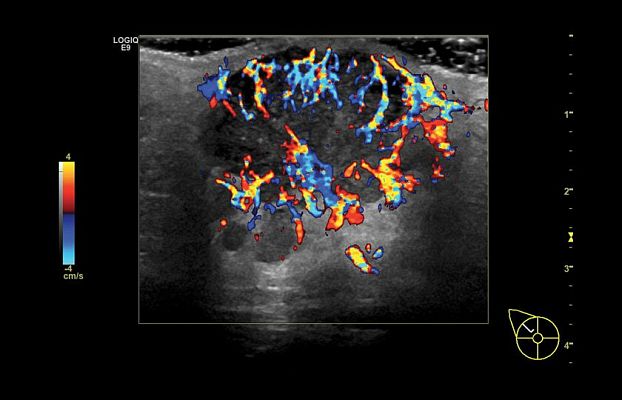

Клинические изображения

- B-Flow и Color B-Flow — технология прямой недопплеровской визуализации кровотока в режиме реального времени, которая позволяет получить гемодинамический профиль с повышенной чувствительностью и разрешением без нежелательных сигналов от окружающих тканей в сосудах всех типов, от крупных, например, сонной артерии, до мелких, например, сосудах паренхиматозных органов.

- Контрастно усиленный ультразвук (CEUS) — использование контрастных препаратов для повышения чувствительности при визуализации кровотока в сосудах.